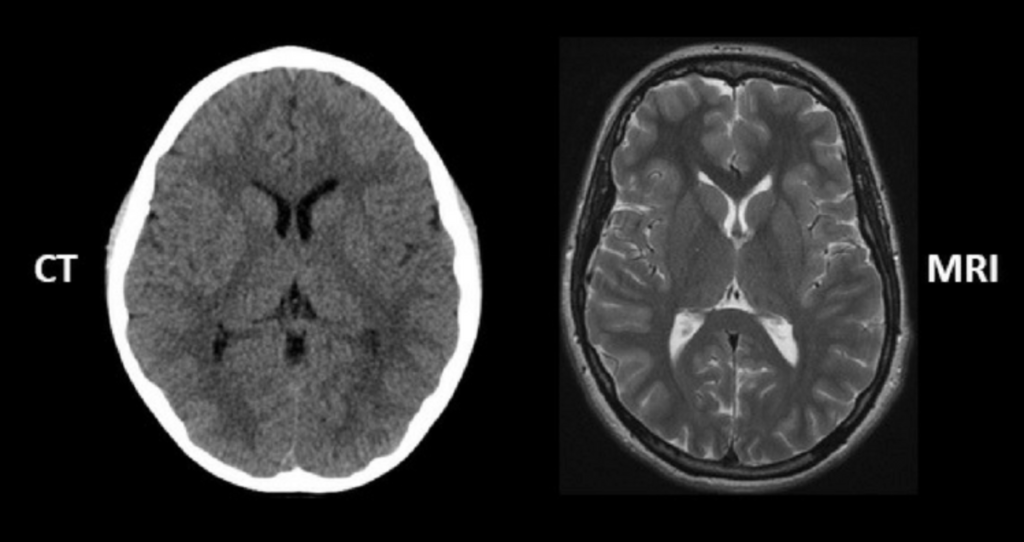

Figure 2. An example of an anatomical image of the brain with CT scan and with an MRI. Image credit: regencymedicalcentre.com